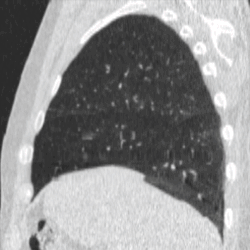

Four-dimensional computed tomography (4DCT) is a type of CT scanning which records multiple images over time. It allows playback of the scan as a video, so that physiological processes can be observed and internal movement can be tracked. The name is derived from the addition of time (as the fourth dimension) to traditional 3D computed tomography. Alternatively, the phase of a particular process, such as respiration, may be considered the fourth dimension.[1]

4DCT is used in radiation therapy planning to reduce doses to healthy organs such as the heart or lungs. Most radiation therapy is planned using the results of a 3D CT scan. A 3D scan largely presents a snapshot of the body at a particular point in time, however due to the time of the acquisition, in which the patient is likely to have moved in some way (even if only breathing), there will be an element of blurring or averaging in the 3D scan.[6] When it comes to treatment planning, this motion can mean there is less accuracy in the positioning of treatment beams, and reduce the likelihood of a repeatable set-up on the linear accelerator when it comes to treatment.[7]

To minimise physical movements of the patient, some sort of immobilisation is typically used. To overcome physiological motion, such as breathing, 4DCT acquires images at a range of times and positions, allowing the extent of motion to be visualised (e.g. from maximum inspiration to maximum exhalation). The treatment plan can then be designed with a knowledge of the full range of possible positions of important organs, and the tumour (target) itself.[8]

4DCT will usually involve a gating technique, such as breathing tracking, so that image acquisition is automatically triggered at set points.[9] This gating can also be applied at treatment, where the radiotherapy beam is only switched on at certain points in the breathing cycle (as in the deep inspiration breath-hold technique).[10]